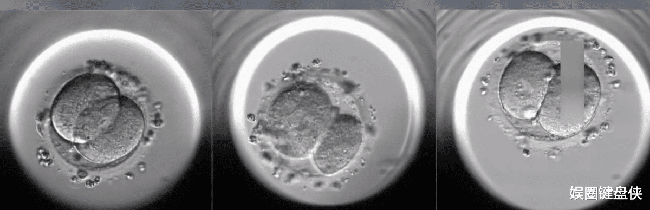

Năm 2003, vợ chồng họ Lý đến tìm gặp tiến sĩ Vương Tiểu Hồng để làm xét nghiệm và thực hiện thụ tinh nhân tạo. Trải qua quá trình chọc hút trứng, bác sĩ cho biết đã lấy được 12 trứng khỏe mạnh từ chị Lý. Đáng mừng hơn nữa, 12 trứng này sau đó đã được thụ tinh thành công với tinh trùng của anh Lý.

Tiếp đến, bác sĩ đã chuyển hai phôi thai vào tử cung của chị Lý. Thật may mắn là một trong hai phôi thai đã có sự phát triển rất tốt. Sau 9 tháng mang thai, chị Lý đã sinh được một bé trai kháu khỉnh và khỏe mạnh.

Trong số 10 phôi thai 12 năm trước thì có 3 phôi kém chất lượng, 7 phôi khỏe mạnh được trữ đông ở bệnh viện. Bác sĩ Vương đã vất vả liên hệ sang tận nước ngoài để đặt mua loại dung dịch rã đông phôi mà thị trường trong nước đã không còn sử dụng.

Quá trình tiến hành rã đông phôi làm tất cả đội ngũ y bác sĩ đều hồi hộp đến nín thở. Sau quá trình rã đông đầy căng thẳng, họ vui mừng thông báo rằng có 3 phôi được rã đông thành công. Ba phôi này được đặt cẩn thận vào lồng ấp mô phỏng nhiệt độ và môi trường của tử cung nhưng sau đó chỉ còn lại 2 phôi có sự phát triển tốt.